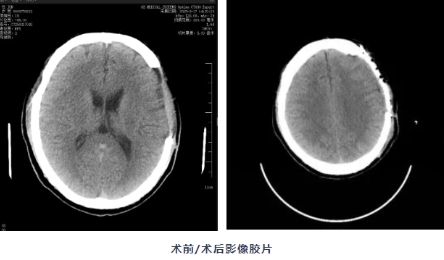

• 直击“医”线|3D打印“补头骨” 颅脑损伤男子重获新生

三维塑形、隔热抗感染等优势,与人体骨骼弹性模量接近,可避免应力性损伤,同时通过3D打印技术“量体裁衣”,制作出的"头骨补丁"与患者头型吻合。此外,该材料性能稳定,可降低术后并发症风险。...